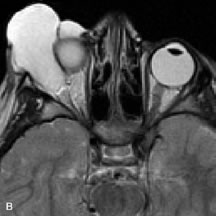

PATIENT PREPARATION Before MRI is performed, patients must be screened and prepared to avoid the potential hazards associated with the strong magnetic field. Patients who have ferrous aneurysm clips or cardiac pacemakers, who depend on life-support equipment, or who retain a possible metallic intraocular foreign body are not candidates for this imaging modality. MRI cannot be performed on obese patients who cannot fit into the bore of the magnet. Patients who are claustrophobic may not tolerate a prolonged period of study within the confines of the magnet, whereas others might do well if given a mild sedative. All worn metallic objects (e.g., necklaces, watches) should be taken off, credit cards set aside, and eye makeup removed before entering the room containing the magnet.5,20,34,35,36 NORMAL ORBITAL ANATOMY T1-weighted images provide the best anatomic details of the orbit because they display superior contrast resolution between normal structures (see Fig. 8). The vitreous has a long T1, resulting in an intermediate signal similar to brain, whereas the crystalline lens and sclera appear dark because of a longer T1 and short T2. The extraocular muscles, like all skeletal muscles, demonstrate a moderately long T1 and short T2 and highly contrast with the intense signal of the surrounding orbital fat (adipose tissue has an extremely short T1). The lacrimal glands appear as mottled areas of reduced intensity of the signal from the orbital fat in the lacrimal fossa. The optic nerves are seen with the same signal intensity as brain white matter and are hypointense relative to the orbital fat because their Tl is longer than the Tl of fat but shorter than the Tl of water. Cortical bone is not well delineated because it contains little free water, yielding minimal signal in MRI, and thus appears dark on all pulse sequences. This feature explains why MR images of the orbital apex and intracanalicular portion of the optic nerves are superior to comparable CT scans. Partial volume averaging of the bones in these regions obscures soft tissue details on CT images, whereas MRI reveals the signals only from the soft tissue structures with no cortical bone input. Bone marrow, on the other hand, is seen as a relatively intense signal because of its high fat content (see Fig. 8).37,38 T2-weighted pulse sequences are not ideal for imaging normal anatomy; however, they are particularly useful in revealing pathologic conditions (see Fig. 9). T2-weighted studies are most easily recognized by a bright vitreous signal. ORBITAL DISEASES Vascular Lesions Cavernous hemangiomas appear as well-circumscribed, smooth, usually intraconal masses that are isointense to muscle on T1-weighted images and hyperintense on T2-weighted images (Fig. 12). Patchy early enhancement is typically followed by diffuse, more homogeneous enhancement.39 The internal architecture of the mass, including septation and internal vasculature, may often be appreciated with high-quality orbital imaging.40 Lymphangiomas consist of ectatic vascular channels within a connective tissue stoma with varying degrees of lymphoid cellularity. On MRI, these tumors are typically poorly circumscribed, multicompartmental, and heterogeneous, often showing cystic dilations with fluid levels (Fig. 13). The signal characteristics within lymphangiomas vary considerably, reflecting cystic and solid components and the varying paramagnetic characteristics of blood at different stages of degradation.40–42 Acute hemorrhage appears hypointense on both T1- and T2-weighted formats. Methemoglobin present in subacute hemorrhage (3 to 14 days) leads to hyperintense signal on both T1- and T2-weighted images.41 A small percentage of lymphangiomas appear radiologically indistinct from orbital cavernous hemangiomas.43 Orbital varices are venous malformations that expand with increased systemic venous pressure, such as with Valsalva maneuvers. Because rapid acquisition of images during a Valsalva maneuver is important in imaging such a lesion, conventional or spiral CT is currently the modality of choice.44 MRI is an excellent modality for demonstrating enlargement of the cavernous sinus and dilation of the superior ophthalmic vein in patients with high-flow carotid-cavernous fistulas (Fig. 14).37MRA may be helpful in the evaluation of the venous outflow pattern. The rapidly flowing blood in these vascular structures carries the excited protons out of the section before they can be imaged, resulting in their dark appearance.5 In low-flow dural arteriovenous malformations, MRA may help define the arterial feeding vessels.45 Neural Lesions MRI is more effective than CT in delineating the intracranial optic nerves, chiasm, and optic tracts and, for this reason, is the preferred imaging modality in the evaluation of optic nerve disorders. The spatial relationships and image contrast of the orbital tissues with intraorbital optic nerve tumors is comparable between the two imaging modalities. The normal nerve is isointense to brain and appears enlarged and kinked owing to infiltration of an optic nerve glioma on T1-weighted images. Gliomas appear hyperintense on T2-weighted images and may be heterogeneous owing to cystic areas within the tumor. Contrast enhancement is variable.46 Intraorbital and intracranial optic nerve sheath meningiomas are usually isointense to cortical gray matter on Tl-weighted images and remain isointense on proton density studies (Fig. 15). Gd-DTPA is useful in delineating the intracranial extension of optic nerve meningiomas.7,47 The hyperostosis of bone and calcification associated with meningiomas are not demonstrated as well on MRI studies as on CT scans.20,37 Gd-DTPA–enhanced MRI also appears promising in the study of the permeability of the blood–brain barrier in selected optic neuropathies.22,48 MRI may reveal an enlarged optic nerve and some degree of contrast enhancement in cases of optic neuritis.49 Muscle Disorders Extraocular muscle enlargement in patients with thyroid-associated orbitopathy is demonstrated equally well with CT and MRI studies. However, the superior tissue contrast on MR images reveals better details of the relationships of the optic nerve to the thickened muscles at the orbital apex (Fig. 16).50 In addition, MRI may be able to differentiate between muscles that are enlarged as a result of edema and active inflammation and those enlarged because of fibrosis by their T2 relaxation times.21 Quantitative MRI was not found to be accurate in predicting the success of low-dose orbital irradiation.51 However, a muscular index relating the diameters of the rectus muscles to the bony orbital dimensions was useful in predicting optic nerve compression.52 MRI is also effective in imaging orbital tumors of mesenchymal origin, such as rhabdomyosarcoma, particularly in the assessment of extension into the anterior and middle cranial fossae (Fig. 17).37 The lack of any pathognomonic radiologic features necessitates rapid orbital biopsy when rhabdomyosarcoma is suspected. Osseous Lesions In general, CT is the imaging modality of choice when details of quantity and quality of bone are needed; however, abnormalities of bones can be detected indirectly by MRI. Cortical bone appears black (signal void) on MR images because of its low proton density and free-water content. The absence or discontinuity of the signal void of the orbital walls may represent bony destruction or fracture. Hyperostosis associated with prostate metastases or meningioma is visualized as areas of black smudging.50,53 Diseases in which the bone is replaced by pathologic tissues with a high free-water content, such as fibrous dysplasia, are well demonstrated on MRI. An intermediate signal intensity on T1-weighted images and hypointense signal on T2-weighted images is representative of fibrous dysplasia. Enhancement on post–Gd-DTPA MR scans is seen and is more evident in areas that are less mineralized.54 Cystic Lesions Dermoid cysts appear as rounded, well-defined lesions typically contiguous with an orbital bony suture. The high-intensity signal on T1-weighted images is attributed to the sebaceous-produced lipid contents (Fig. 18).31,50 Mucoceles may demonstrate a hypointense or hyperintense signal on MR images, depending on the concentration of proteinaceous or inflammatory fluid components. The integrity of the bony walls of the expanded sinus cavities cannot be assessed on MR as well as by CT.37,50,55,56 A high-signal intensity on Tl- and T2-weighted images is characteristic of orbital chronic hematic cysts because of the blood-breakdown products within the cysts.57 Trauma Although soft tissue relationships are usually better demonstrated on MRI, the evaluation of craniofacial bony trauma is preferable with CT. For example, prolapse of orbital fat through a fracture site and hemorrhage of adjacent tissues are demonstrated in an MR image, but the actual fractured bone is not imaged. Three-dimensional MRI of the orbit in subacute trauma has been described,58 although its precise role is not currently established. MRI has been suggested to be superior to CT in detecting intraorbital wooden foreign bodies.59,60 In a series of penetrating orbital injuries with organic foreign bodies, however, MRI was able to identify the foreign body in only four of seven cases.61 With an in vitro model for wood foreign body, McGuckin and colleagues concluded that CT was the imaging modality of choice.62 A careful history and, in selected cases, plain films to rule out a metallic foreign body are crucial before MRI is considered in patients with periocular trauma. MRI is particularly helpful in the detection and characterization of subperiosteal hematomas of the orbit (Fig. 19). They are most commonly seen in the subperiosteal space of the superior orbit as well-defined masses following a traumatic injury. The signal intensity varies depending on the acute, subacute, or chronic nature of the hematoma, based on the stage of blood degradation. Fresh hemorrhages are hypointense on T1-weighted images and hyperintense on T2 images. Hematomas that are 1 to 7 days old are hypointense on both T1- and T2-weighted images. T1-weighted images of hematomas more than a week old are hyperintense due to the oxidation of deoxyhemoglobin to methemoglobin, whereas the T2 images remain hypointense.63 Metastatic Tumors Breast carcinoma metastatic to the orbit has been demonstrated to be hypointense to the surrounding orbital fat on T1-weighted studies and hyperintense on T2-weighted images and has an affinity to the extraocular muscles (Fig. 20).50,64 The MRI characteristics of prostate carcinoma metastatic to the orbit have been described as involving the greater and lesser wing of the sphenoid, orbital roof, and optic canal. Diffuse bone hypertrophy with isointense or slightly hyperintense tissue on T1-weighted images represents the osteoblastic carcinomatous bone infiltration. Contrast enhancement is variable on T1-weighted and fat-suppressed images.65 Most other metastatic tumors also have a lower intensity signal on T1-weighted images and appear to displace or infiltrate normal orbital structures; however, their signal characteristics are variable on T2-weighted MR images.66 Many metastatic tumors demonstrate bright contrast enhancement with Gd-DTPA. Infectious Disorders MRI findings of preseptal and orbital cellulitis typically include increased signal intensities on T2-weighted images of the eyelids and orbital fat, respectively, due to the increased water content of the tissues. Since most cases of bacterial orbital cellulitis are associated with paranasal sinusitis, hyperintense signals of the affected sinuses may also be found on T2-weighted images as well as enhancement of polyps and granulation tissue on postgadolinium T1-weighted MR images. Subperiosteal abscess formation may occur due to contiguous spread of infection from the paranasal sinuses and appear on MRI as an area of intermediate signal on T1-weighted and proton-weighted MR images. The abscess may appear slightly hyperintense compared with muscle on T2-weighted scans with the necrotic contents having the greatest intensity.67 MRI and MRV are more sensitive than CT in revealing cavernous sinus thrombosis. Engorgement of the cavernous sinus, extraocular muscles, and ophthalmic veins is seen with hyperintensity of the thrombosed sinuses evident on all pulse sequences. The enlarged, thrombosed superior ophthalmic vein appears less hypointense than the normal contralateral ophthalmic vein, and hyperintensity within the lumen of the vessel may be seen on T1- and T2-weighted MR images.68 Inflammatory and Lymphoproliferative Lesions Inflammatory conditions of the orbit, both idiopathic (inflammatory pseudotumor) and those of known causes, have been found to be hypointense to fat and isointense to muscle on Tl-weighted studies and isointense or slightly hyperintense to fat on T2-weighted images (Fig. 21).50,64,69 The more fibrous or sclerosing varieties have less signal intensity on T2-weighted images. Marked enhancement is seen in pseudotumor infiltrates after gadolinium administration.70 The same signal characteristics are demonstrated in patients with Tolosa-Hunt syndrome, with mass lesions seen in the cavernous sinuses and orbital apices.71 Lymphomas have MRI characteristics similar to those of inflammatory lesions in that they are hypointense to fat and isointense to muscle on T1-weighted images (Fig. 22). They may appear hyperintense to fat on T2-weighted images, perhaps owing to less fibrosis than that seen in orbital inflammatory pseudotumor, although this is not a consistent finding.31,50,66 Lymphoid tumors typically enhance moderately after contrast injection. Unfortunately, studies have shown that tumor density and homogeneity are similar between inflammatory and malignant orbital infiltrates, and MRI cannot differentiate these lesions.72,73 Lacrimal Gland Tumors Lacrimal gland lesions present special problems in diagnosis and management. Pleomorphic adenoma (benign mixed tumor) should not be biopsied, but rather excised in toto. On the other hand, for lymphoma and inflammatory infiltrates, incisional biopsy is more appropriate than complete excision of the lacrimal gland. Thus, preoperative clinical and radiologic evaluation are especially crucial in planning appropriate surgical management. Pleomorphic adenomas demonstrate long T1 and T2 signal characteristics. They may show heterogeneity on T2-weighted images74 and moderate to marked enhancement with contrast.75 Signal characteristics of adenoid cystic carcinoma include hypointensity to fat on T1-weighted images, hyperintensity to fat with increased T2 weighting, and isointensity to fat on proton density-weighted studies (Fig. 23).31,75 Secondary bony alterations of the lacrimal fossa associated with lacrimal gland tumors, such as remodeling (benign mixed tumor) or destruction (adenoid cystic carcinoma), are seen indirectly on MR images; however, bone windows on CT scans provide better delineation of these changes. In contrast to the round or globular appearance of benign or malignant epithelial tumors of the lacrimal gland, lymphoproliferative tumors usually appear to be molding or draping onto the globe and the surrounding bony orbit. LACRIMAL DRAINAGE SYSTEM DISORDERS MRI with surface coils provides excellent spatial resolution and tissue-specific signal intensities of the lacrimal drainage system. These parameters have been found useful to more accurately demonstrate the extent of lesions in the lacrimal sac and differentiate long-standing mucoceles from solid tumors than CT.76 Physiologic studies in patients with tearing disorders now include MR dacryocystography, in which Gd-DTPA is either placed topically in the conjunctival fornix or injected by cannulation into the lacrimal sac. They provide a detailed morphologic and functional analysis of the lacrimal excretory system; however, they are no more sensitive than digital-subtraction dacryocystography or CT dacryocystography.77–79 INTRAOCULAR TUMORS On MRI, uveal melanomas have a typical appearance that helps to differentiate them from other primary and secondary intraocular tumors as well as choroidal detachments. Pigmented melanomas are hyperintense on Tl-weighted images, hypointense on T2-weighted studies, and hyperintense on proton density–weighted examinations (Fig. 24).30,31,50,80–82 These signal characteristics have been attributed to the paramagnetic properties of melanin because of stable free radicals that shorten the T1 and T2 relaxation times. Moderate enhancement is seen on postgadolinium T2-weighted images. Gadolinium-enhanced T1-weighted images are particularly sensitive in detecting choroidal melanomas.83 MRI may be less sensitive in detecting extrascleral extension of tumor than echography performed by an experienced ultrasonographer.84 Tumors metastatic to the choroid are hyperintense on T1- and T2-weighted images.24 The signal characteristics, however, may be similar to those seen with choroidal melanoma. Choroidal hemangiomas, on the other hand, have an intermediate signal on T1-weighted sequences and become hyperintense on T2-weighted images50 as well as proton density–weighted images.81 Retinoblastomas display moderate signal intensity on T1-weighted studies and a low signal on T2-weighted images.31,80,85 Calcification can be easily detected by CT and ocular ultrasonography but is not imaged by MRI.25,50 The presence of optic nerve involvement is best evaluated by MRI. ACQUIRED ANOPHTHALMIA When an eye is removed owing to tumor or trauma, an implant is typically placed in the intraconal space. MRI may be useful in defining the size, shape, and position of such orbital implants.86 Porous hydroxyapatite or polyethylene implants are preferred by many surgeons performing enucleation or evisceration. A porous implant offers the possibility of supporting a motility coupling peg to increase the movement of the overlying prosthesis. MRI with contrast is used by some surgeons to evaluate the degree of fibrovascular ingrowth in hydroxyapatite87 and porous polyethylene88 implants prior to motility peg placement. |